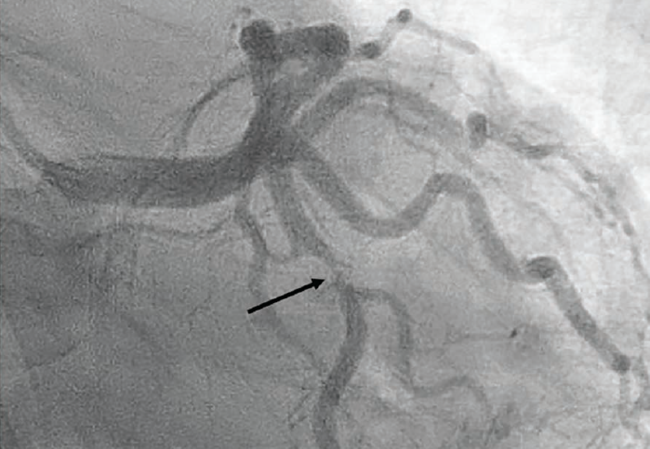

To aid intravascular ultrasound (IVUS) catheter delivery, the mid LCx was predilated with a compliant 2.5 mm x 15 mm balloon dilatation catheter at high pressures (16 atmospheres [atm]). However, the IVUS catheter could not traverse past the proximal LCx bend due to the acute angle and tortuosity, and was withdrawn. With no angiographic evidence of calcification, lithotripsy or atherectomy was deemed unnecessary, with adequate expansion confirmed in two orthogonal views. We proceeded with stenting the mid to proximal LCx using a 2.75 mm x 18 mm Xience Skypoint drug-eluting stent (Abbott), deployed at 14 atm. Post dilation was performed using a 3.0 mm x 8 mm noncompliant balloon, serially inflated to a maximum of 14 atm in the proximal and mid portions. Final angiography revealed TIMI-III flow, no evidence of proximal or distal edge dissections, no perforation, and minimal residual stenosis (Figure 3). At the end of case, all catheters and wires were removed, and hemostasis of the right radial artery was seamlessly and successfully achieved using a TR Band™ Radial Compression Device. The total contrast volume used was 150 mL, with a case duration of 1.3 hours. The patient was discharged the next day without complications and is doing well on follow up. Her discharge medications included a minimum of one year of aspirin 81 mg daily and clopidogrel 75 mg daily.